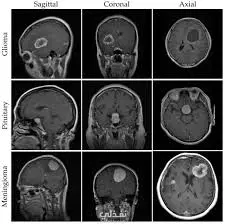

قمت بتطوير نموذج ذكي باستخدام تقنيات تعلم الآلة والتعلم العميق لتصنيف صور أشعة الدماغ (MRI) والكشف عن وجود أورام في المخ، مع إمكانية التمييز بين الحالات المصابة وغير المصابة بدقة عالية، بهدف دعم التشخيص الطبي وتسريع اتخاذ القرار. تفاصيل تنفيذ المشروع: الأدوات والتقنيات المستخدمة: لغة البرمجة Python. مكتبات TensorFlow و Keras لبناء النماذج العميقة. مكتبات NumPy و Pandas و Matplotlib لمعالجة وتصور البيانات. تقنيات Convolutional Neural Networks (CNN) نوع البيانات: صور أشعة الرنين المغناطيسي (MRI) للمخ. الصور باللون الرمادي (Grayscale) مجموعة بيانات تحتوي على صور مصنفة (Labelled Data) لحالات سليمة وحالات مصابة بأورام، مما يستدعي دقة عالية في المعالجة. تحليل ومعالجة البيانات: تحليل البيانات الاستكشافي (EDA) لفهم توزيع الفئات داخل البيانات. تنظيف البيانات وتجهيزها (Data Cleaning & Preprocessing) لضمان جودة المدخلات. تطبيق المعالجة المسبقة على الصور (Image Preprocessing) مثل توحيد الأبعاد (Resizing) والمعايرة (Normalization) لتناسب مدخلات الشبكة العصبية. تحسين جودة البيانات لرفع كفاءة النموذج وتقليل الـ Overfitting آلية عمل النموذج: تم استخدام خوارزميات الشبكات العصبية الالتفافية (CNN) المتخصصة في الرؤية الحاسوبية (Computer Vision) لبناء نموذج قوي. استخراج الخصائص الدقيقة من الصور (Feature Extraction) للتعرف على الأنماط المرتبطة بالأورام. تصنيف الحالات بدقة (Classification) لتحديد ما إذا كانت الأشعة تحتوي على ورم أم لا. نتائج المشروع: حقق النموذج دقة عالية في اكتشاف أورام المخ، وتصنيف نوعه بناءً على تحليل صور الأشعة هذا المشروع خطوة فعّالة نحو تسخير الذكاء الاصطناعي لدعم المجال الطبي وتحسين سرعة ودقة التشخيص لصالح المرضى.